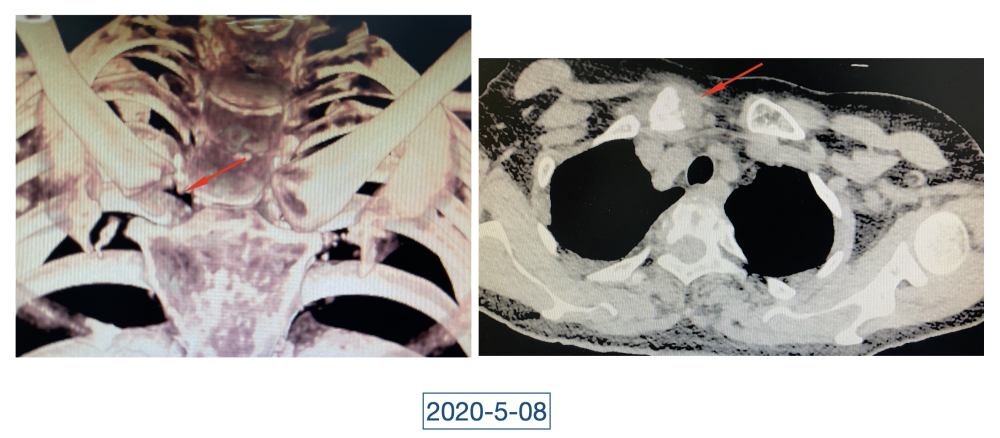

经过科室讨论、会诊,李辉也查阅了很多资料,按照黄大娘的症状,他跟之前的接诊医生一样,觉得应该是骨关节感染。可之前的穿刺、培养各种检查也做过,为什么没有找到致病菌?李辉想,或许是检查中出现了问题,没有查对地方。于是他决定,在B超引导下骨穿刺,通过最新技术精准定位病灶,只有这样也许才能抓到真正的“罪犯”。

在黄大娘入院第四天,李辉将她推入检查室,结果很快出来了,为烟曲霉菌感染。这个结果验证了李辉的想法,也解释了此前抗感染药物为何一直不奏效。“找到元凶就好办了,对症用药就可以。真菌感染本来治疗时间就很长,骨科类感染灶治疗时间更长,用了5个月的时间,终于治好了。”

近日随访得知黄大娘身体好转,李辉脸上的笑容掩饰不住,他说,据查阅文献,11处感染灶,这是全世界感染灶最多的骨关节感染,但现在,这罕见、复杂的病已经被治愈。